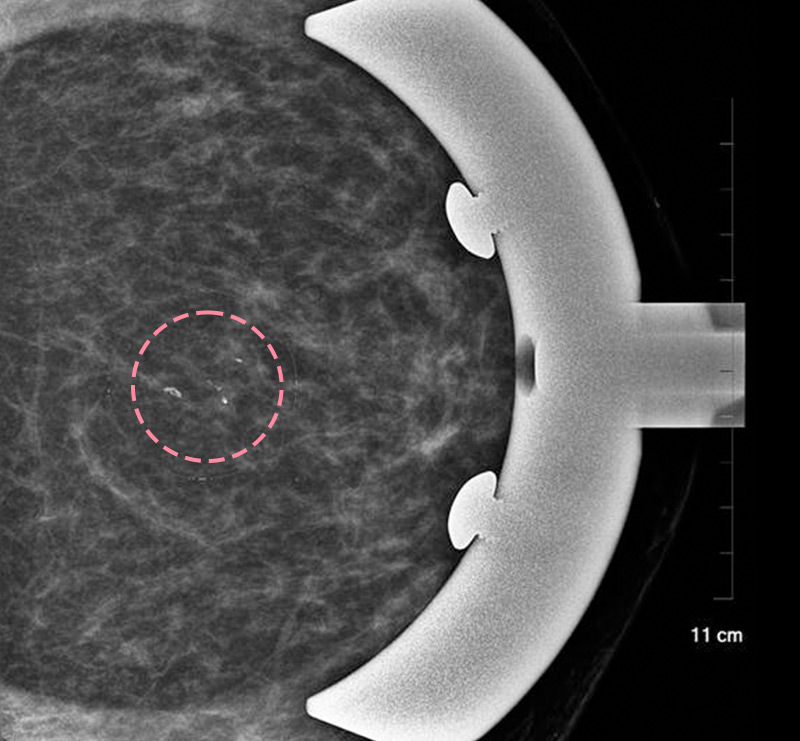

매우 빠르게 자라는 유방 종양 수술을 위해 외국에서 내원한 17세 환자의 사례입니다.

3cm 이상의 유방 종양은 외과적 수술로 제거하는 것이 원칙이고, 대부분의 경우 대학병원으로 연계됩니다.

그러나 한송이 원장은 대학병원에서의 고난도 시술 경력을 다수 보유하고 있어 크기가 큰 종양도 맘모톰 시술로 가능하였습니다.

3번에 걸쳐 맘모톰시술을 시행한 결과 성공적으로 제거를 마칠 수 있었습니다. 외과적 절제로 생길 수 있었을 흉터를 원치 않으셨던 환자와 보호자분 모두 시술 결과에 만족하셨습니다. 매년 추적 검사를 시행하고 있으며, 깨끗이 제거된 상태를 잘 유지하는 중입니다.